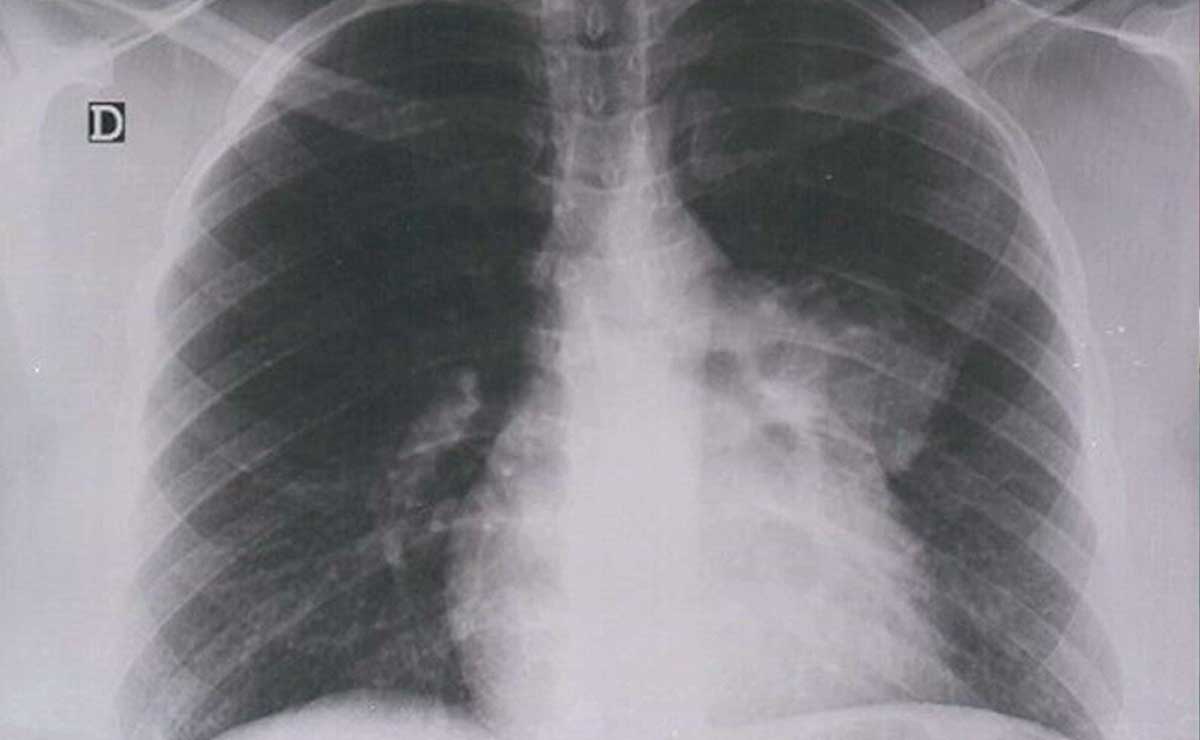

José Antonio Martínez García, secretario de Salud estatal, reveló que en Puebla el primer tipo de cáncer que causa mortalidad, tanto en hombres como en mujeres, es el de pulmón.

En conferencia de prensa, en el marco del 19 de octubre, Día Internacional de la Lucha contra el Cáncer de Mama, dijo que el cáncer de pulmón ocupa el primer lugar en causa de mortalidad en el estado.